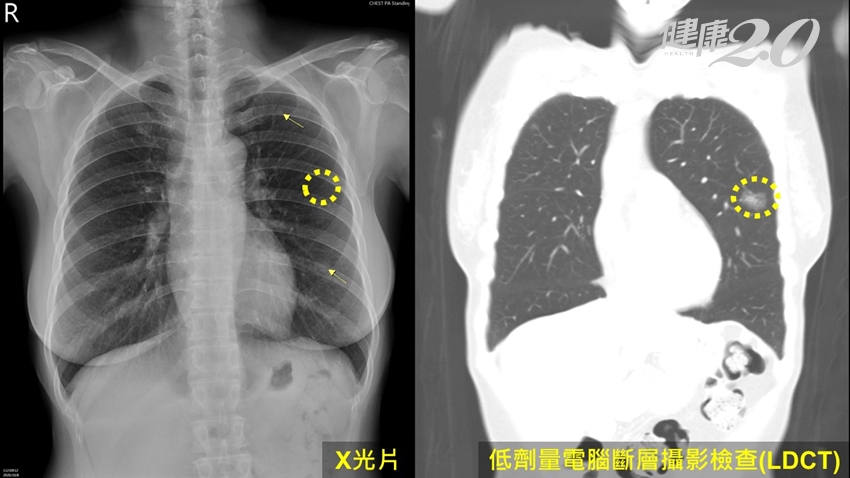

▲蘇英傑醫師指出,X光攝影檢查有盲點,較難發現早期肺癌。

更令人吃驚的是,這106位肺癌病人,共進行了118例手術,切除155顆肺癌之中,X光攝影檢查所能看到的肺癌比率,竟然只有22%,有高達78%的肺癌只能透過電腦斷層掃描當中發現,X光攝影檢查的診出率出奇的低。